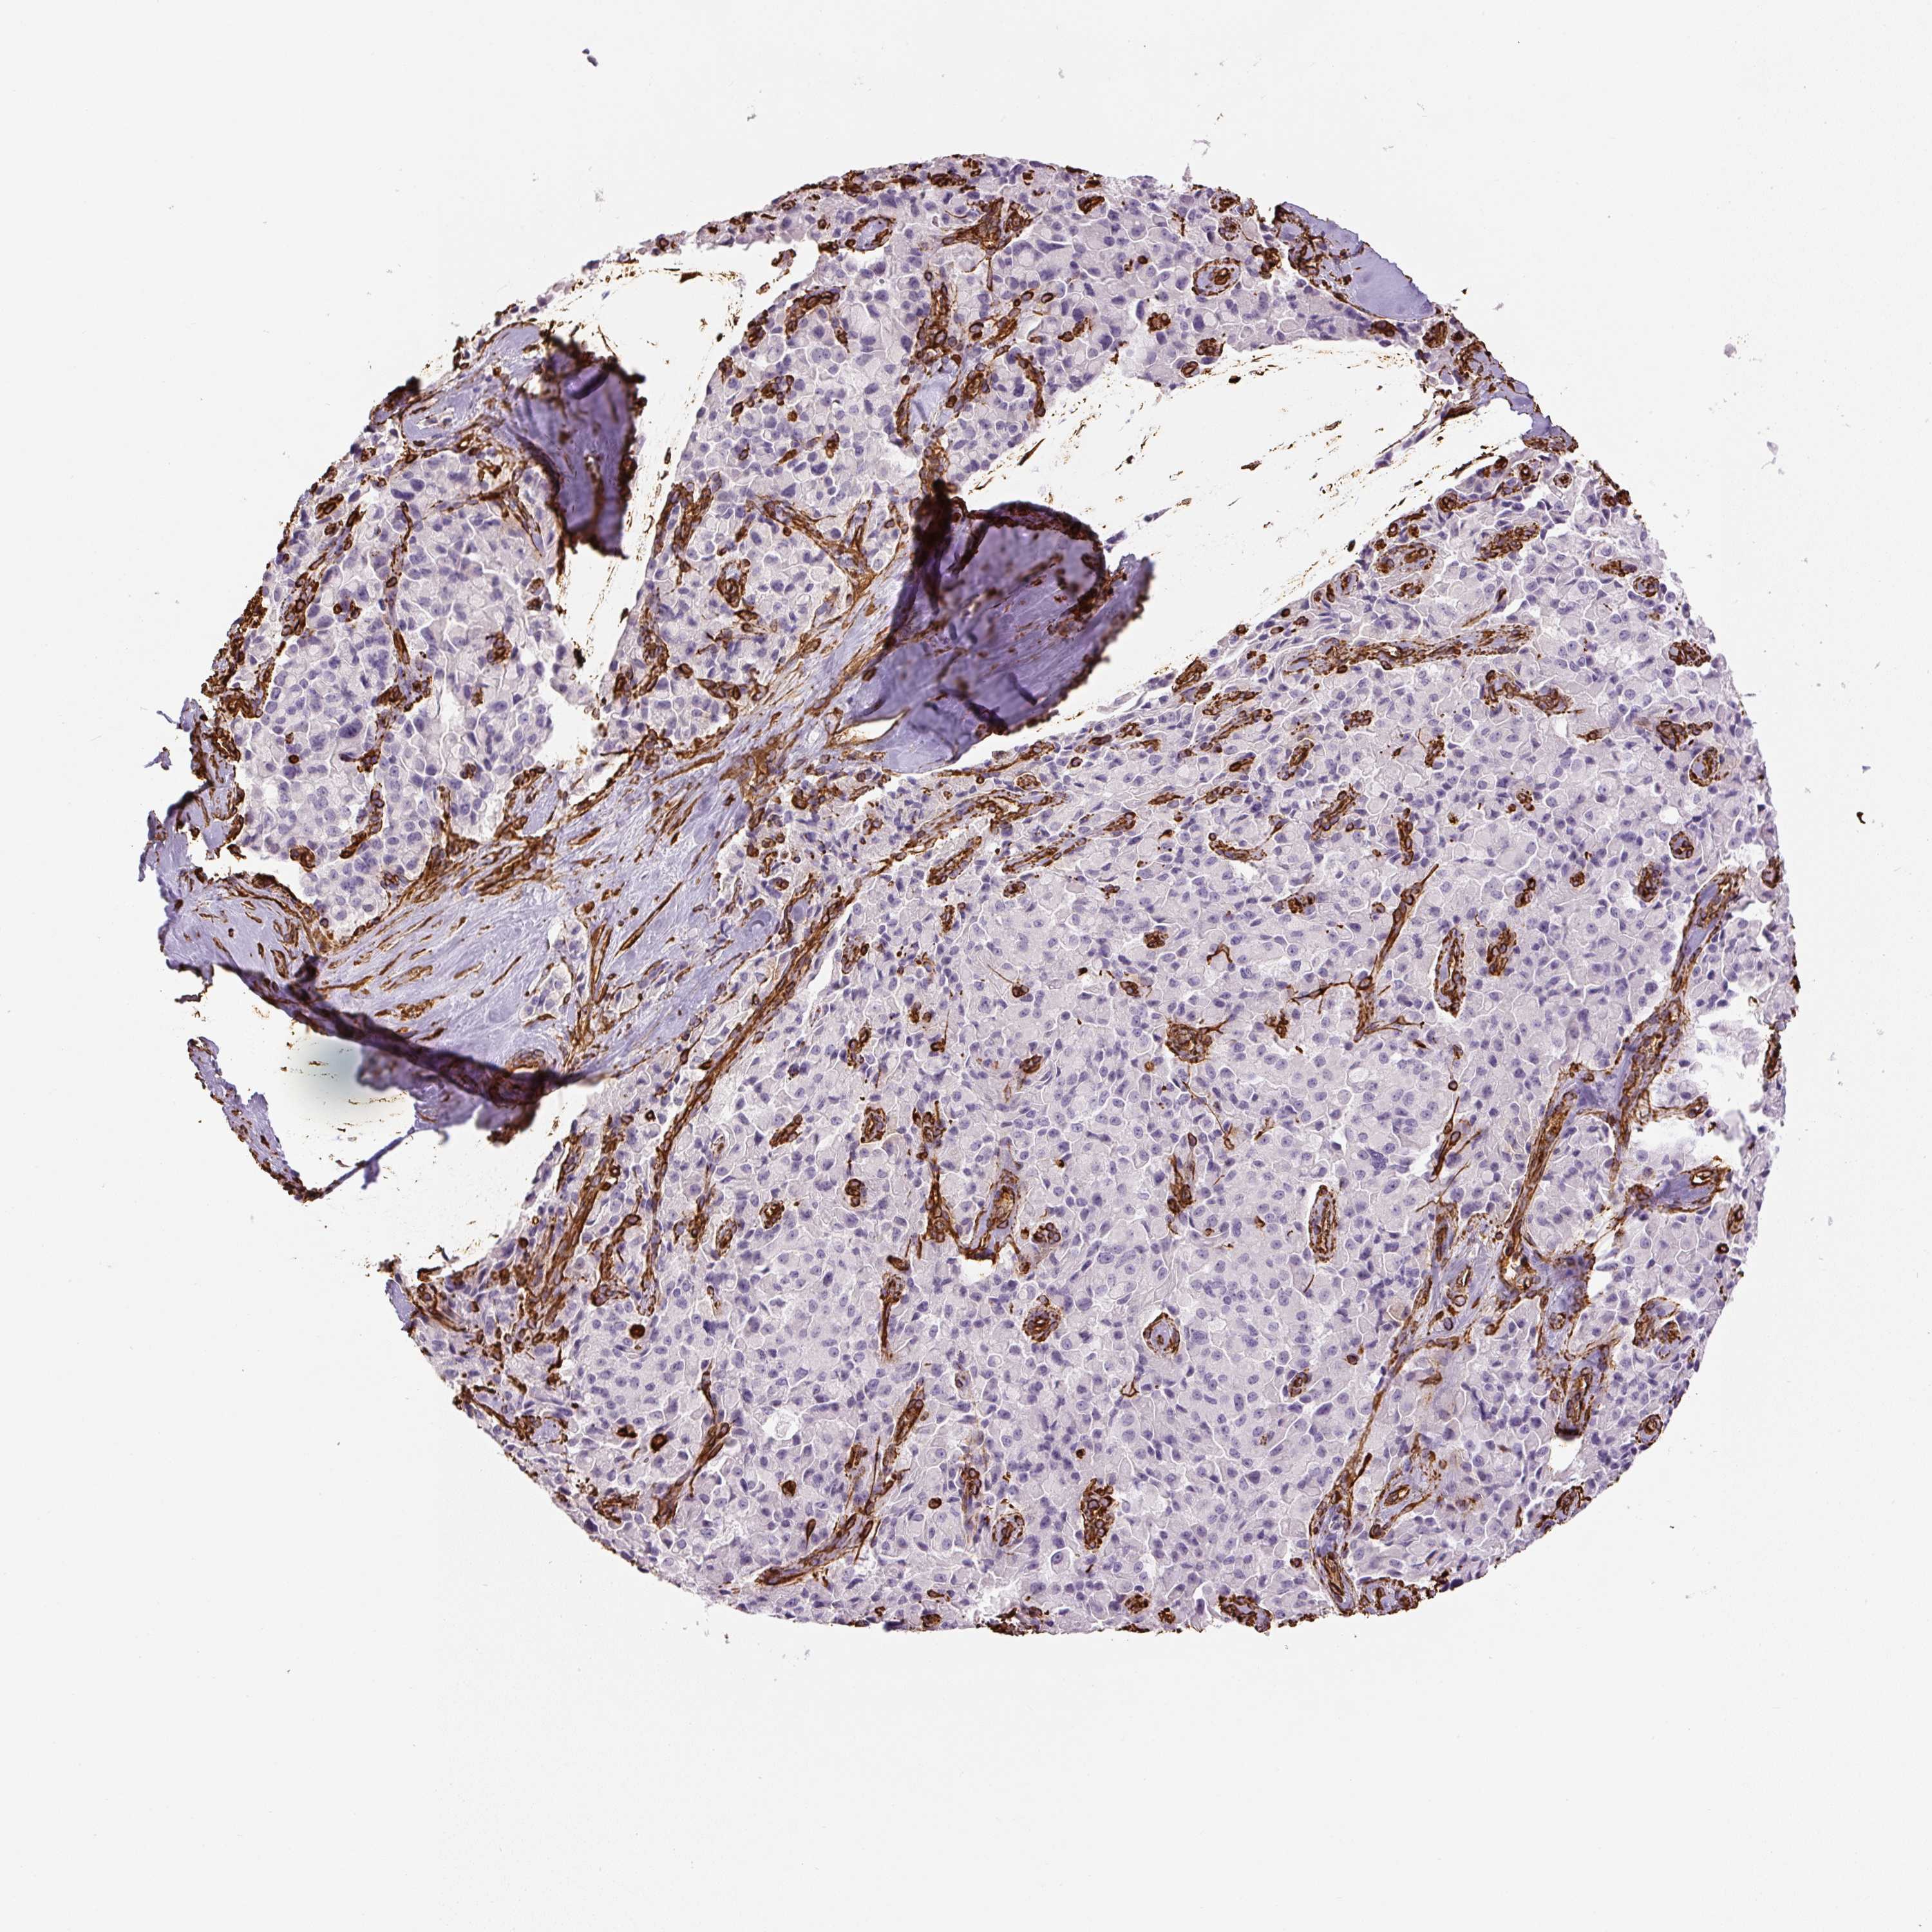

PANCREATIC CANCER - Protein expressioni

A mouse-over function shows sample information and annotation data. Click on an image to view it in a full screen mode. Samples can be filtered based on level of antibody staining by selecting one or several of the following categories: high, medium, low and not detected. The assay and annotation is described here.

Note that samples used for immunohistochemistry by the Human Protein Atlas do not correspond to samples in the TCGA dataset.

Antibody stainingi

Antibody staining in the annotated cell types in the current human tissue is reported as not detected, low, medium, or high, based on conventional immunohistochemistry profiling in selected tissues. This score is based on the combination of the staining intensity and fraction of stained cells.

Each image is clickable and will lead to virtual microscopy that enables deeper exploration of all samples and also displays staining intensity scores, fraction scores and subcellular localization as well as patient and tissue information for each sample.

Antibody HPA001762

Antibody CAB000080

Antibody CAB058687

Staining

High

Medium

Low

Not detected

Intensity

Strong

Moderate

Weak

Negative

Quantity

>75%

75%-25%

<25%

None

Location

Nuclear

Cytoplasmic/membranous

Cytoplasmic/membranous,nuclear

Adenocarcinoma, NOS

Adenocarcinoma, metastatic, NOS